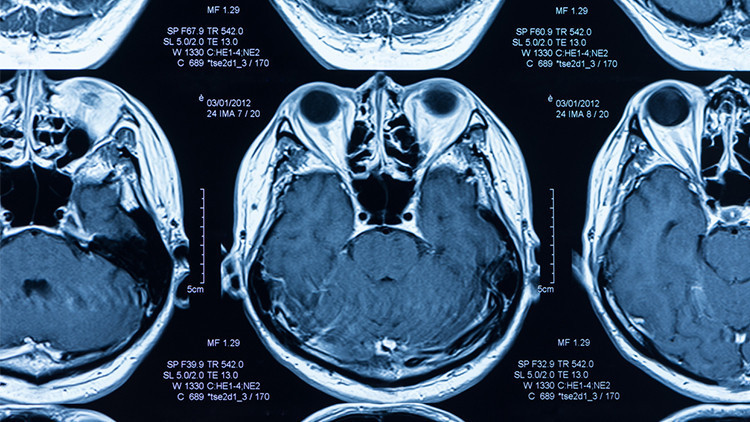

Enfeksiyondan önce ve sonra yapılan beyin taramaları, Covid geçiren kişilerde, geçirmeyenlere göre daha fazla gri madde kaybı ve doku hasarı olduğunu ortaya koydu.

Tüm katılımcılara bu çalışma için ikinci bir beyin görüntüleme yapıldı. Hasta grubunda bu görüntüleme hastalık geçirdikten ortalama 141 gün sonraydı. Ayrıca hastaların bilişsel fonksiyonlarını değerlendirmek için bazı testler de gerçekleştirildi.

DOKU HASARLARI ORTAYA ÇIKTI

Araştırmanın sonuçlarını yorumlayan Nöroloji Uzmanı Prof. Dr. Dilek Necioğlu Örken, “Bu MR taramaları Covid-19 geçiren kişilerin beyinlerinde belirgin büzülme kalıpları ortaya çıkardı. Kontrol grubu ile karşılaştırıldığında orbitofrontal korteks dediğimiz göz yuvalarının hemen üzerinde yer alan, duygu ve hafıza ile ilgili beyin alanlarından sinyaller alarak karar vermede önemli bir rol oynayan bölgede ve beynin ortasında yer alan ve hafıza ile ilgili bir yapı olan hipokampusu çevreleyen parahipokampal girusta gri madde kalınlığında ve doku kontrastında azalma saptandı” diyor ve ekliyor:

“Çalışmacılar burundaki koku algılayan nöronlardan alınan duyusal bilgiyi birincil koku korteksine götüren yapılarda da doku hasarını ortaya çıkardı. Bir diğer bulgu genel beyin boyutunda da küçülme görülmesiydi. Yapılan testlerde enfekte olmuş katılımcılar ayrıca iki zaman noktası arasında ortalama olarak daha belirgin zihinsel düşüş gösterdi. Beyin kabuğu dediğimiz gri madde bu sayılan alanlarda dikkat, hafıza, dil becerileri ve yürütücü işlevler gibi pek çok yüksek kortikal fonksiyonların işlendiği ve depolandığı alanlardır. Bunların kaybında artış bu işlevlerimizi bozabilir."

-- Bugüne kadar Covid-19 ile ilgili beyin görüntüleme çalışmalarının çoğu akut vakalarda yapıldı. BT, PET veya MRG taramalarında ak madde lezyonları, beyin kanlanmasında azalma ve iskemik lezyonlar gösterildi. Ancak hastalık sırasında yapıldıkları için bulguların enfeksiyondan önce olup olmadığı kesin olarak bilinmiyordu.

-- İşte bu çalışmanın en önemli ve güçlü yönlerinden biri hastaların Covid-19 enfeksiyonu öncesinde beyin MR’larının çekilmiş olması ve karşılaştırmanın bu MR’lar ile yapılması.